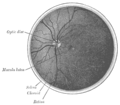

The interior of the posterior half of the left eyeball.

A fundus photograph showing the macula as a spot to the left. The optic disc is the area on the right where blood vessels converge. The grey, more diffuse spot in the centre is a shadow artifact.